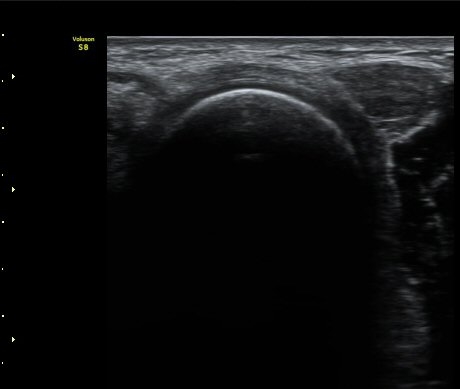

ÆÈ²ÞÄ¡  ¾ÕÂÊ¿¡¼­ ½ÃÇàÇÑ ¿ä°ñµÎ Á¾´Ü¸é°Ë»ç¿¡¼­ ƯÀÌ ¼Ò°ßÀ» º¸ÀÌÁö ¾ÊÀ½(±×¸² 1).